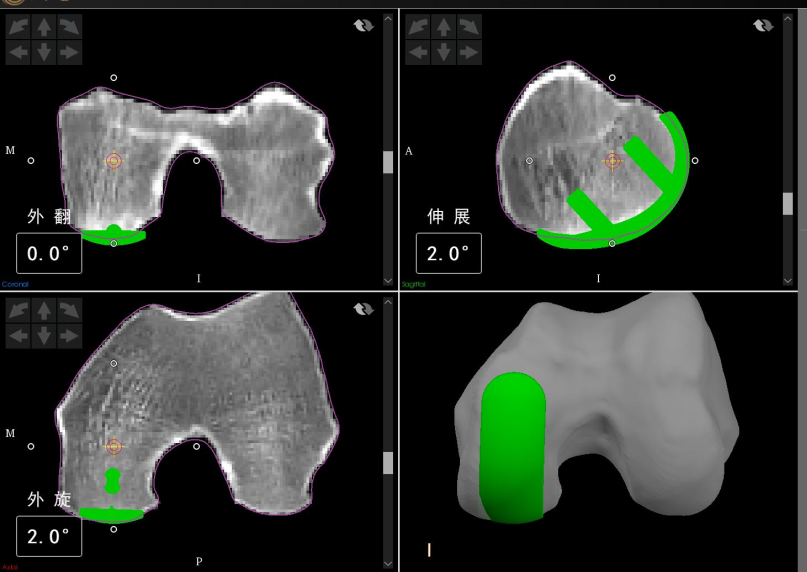

术前,骨科中心副主任、关节外科副主任张鹏带领关节外科单髁置换团队召开会议,进行详细术前规划:首先通过患者下肢CT扫描数据进行建模,通过三维和二维模型直观地识别患者解剖标志点,为患者精确确定假体型号和理想位置。

手术过程严格按照标准机器人手术计划进行。术中经过再次配准后,根据术中关节软组织张力情况微调手术方案,经过机械臂完美地将手术方案“复制”到患侧膝关节,真正实现了亚毫米级截骨。